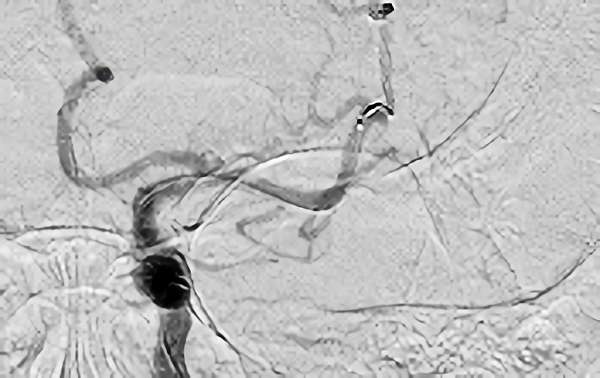

血管内治療 手術実績

症例 '18年5月

No.

118

'18年5月5日

心原性脳梗塞

80代

院内外来

手術写真

治療

前

中

後

手術日